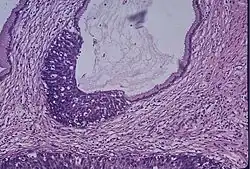

Microscope image of the cervical gland showing an area of high grade epithelial dysplasia.

Cervical cancer is the fourth most common cancer for women with an estimated 340,000 deaths according to the World Health Organization (WHO).[27] HPV disease is the leading cause of cervical cancer, therefore making the HPV vaccine the primary prevention measure for the cancer. Screening with the Papanicolaou (Pap) test is consequently the second measure of prevention.[27] The test identifies cells that are precancerous, and are often credited for the reduced mortality.[28]